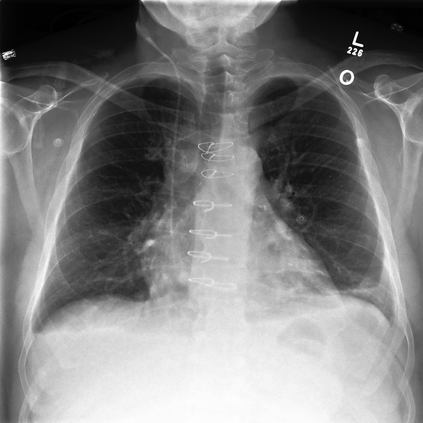

To address these issues, we propose a novel Adaptive patch-word Matching (AdaMatch) model to correlate chest X-ray (CXR) image regions with words in medical reports and apply it to CXR-report generation to provide explainability for the generation process. AdaMatch exploits the fine-grained relation between adaptive patches and words to provide explanations of specific image regions with corresponding words. To capture the abnormal regions of varying sizes and positions, we introduce the Adaptive Patch extraction (AdaPatch) module to acquire the adaptive patches for these regions adaptively. In order to provide explicit explainability for CXR-report generation task, we propose an AdaMatch-based bidirectional large language model for Cyclic CXR-report generation (AdaMatch-Cyclic). It employs the AdaMatch to obtain the keywords for CXR images and `keypatches' for medical reports as hints to guide CXR-report generation. Extensive experiments on two publicly available CXR datasets prove the effectiveness of our method and its superior performance to existing methods.